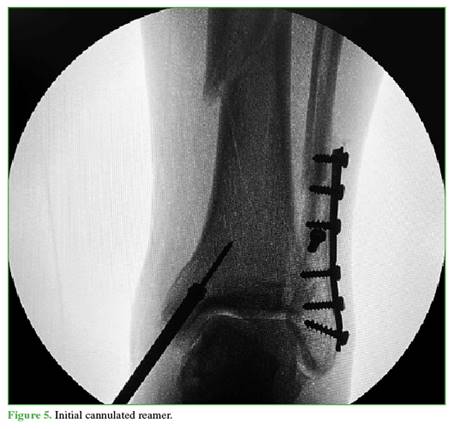

A 3 cm incision is then made distally from the tip of the tibial malleolus (Figure 2). Using a guidewire, the entry point is identified in the center of the tibial malleolus in both planes (Figures 3 and 4), and then enlarged with a cannulated reamer (Figure 5). An olive-tipped guidewire is inserted (Figure 6), and reaming of the medullary canal is performed through a soft tissue protector (Figure 7).